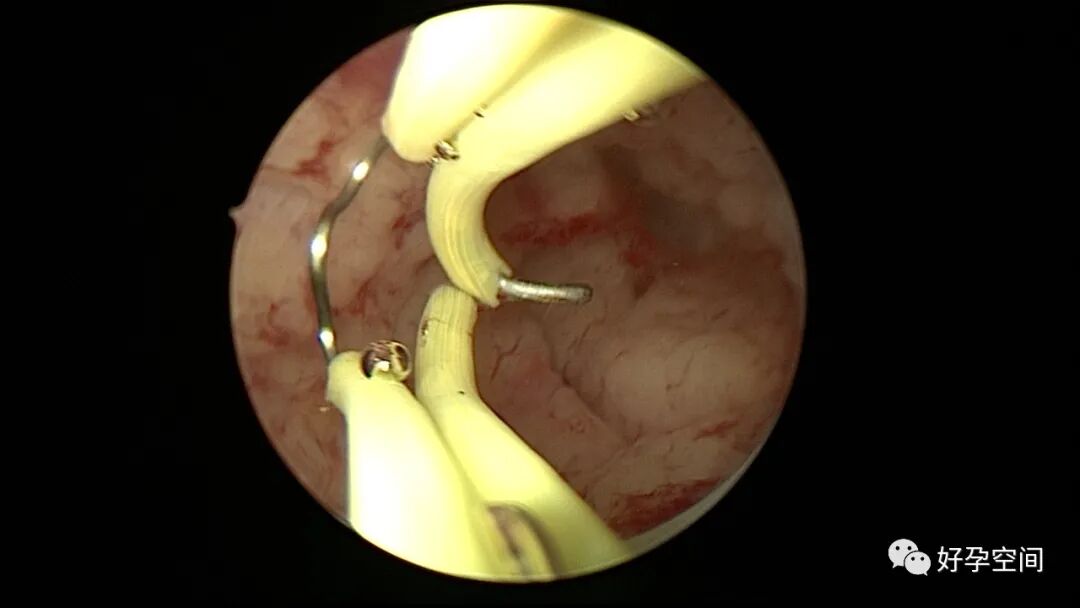

病例2:患者31岁,原发不孕,2019年11月在重庆某妇幼保健院做宫腹腔镜手术疏通输卵管,术中未取内膜活检,术后未孕。2021年7月在成都某大型生殖中心试管怀孕双胎(移植前未做宫腔镜检查及内膜活检),2021年11月孕4月双胎破水,在达州当地医院引产清宫,清宫术后40天复诊B超提示宫腔胚物残留。2022年1月到我院(眉山蕴缨妇产医院)行宫腔镜手术切除残留组织,2022年4月宫腔镜术后3个月复诊B超提示宫腔粘连,再次来我院行宫腔镜分粘。宫腔被覆一层沙丘状质脆增生组织,宫腔下段两侧壁内聚,行分粘术,取内膜送病检。

子宫内膜结核是由结核分枝杆菌在子宫内膜部位种植引起的炎症,是仅次于输卵管结核的常见女性生殖器结核。子宫内膜结核常由输卵管结核蔓延而来,多继发于盆腔腹膜结核或肺结核。子宫内膜结核的超声表现主要为:子宫内膜回声不均匀、宫腔内结节样病灶、宫腔内强回声灶、单纯的子宫内膜薄等。盆腹腔超声显示输卵管炎性表现:输卵管增粗、肥厚、扭曲、僵硬、输卵管积液积脓、卵巢旁混合性包块、输卵管系膜囊肿、盆腔包裹性积液等。术中所见:盆腹腔组织粘连、盆腹腔粟粒样结节、结核球、脓肿等,输卵管伞端烟斗样外翻,输卵管内充满淡黄色干酪样或豆渣样组织。宫腔镜显示宫腔狭窄、宫壁僵硬、宫内膜肉芽肿样增生、内膜质脆易刮除、干酪样组织、脓液等。

温宝宁等将子宫内膜结核宫腔镜检查的镜下表现分为:①宫腔形态、大小正常,双侧输卵管开口可见,子宫内膜发红、增厚,局部突起,表面可见少量质脆的小颗粒状赘生物,可刮出质脆的子宫内膜组织;②宫腔形态正常,但是宫腔内无正常子宫内膜,均被覆一层苍白的绒毛状或棉絮状质脆组织,血管少,无异形血管,宫腔内病灶与正常组织分界明显;③宫腔形态异常,呈窄桶状,子宫内膜瘢痕化,输卵管开口细小,甚至宫角消失。